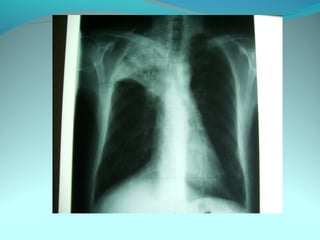

Opacité occupant la partie externe du 1/3 infer du poumon droit

dense et homogene ovalaire de 8cm de grand axe vertical

La limite externe se confend avec une opacité d’environ 1cm comble

les coupole costodiaphragmatique droit

Limitée a sa partie sup par la petit sessure qui est epaisse et pas de

lyse costale

 DIAGNOSTIC :DIAGNOSTIC :

 1_1_cancer bronchique droit( d epaississement)

 2_2_ kyste hydatique au stade sain